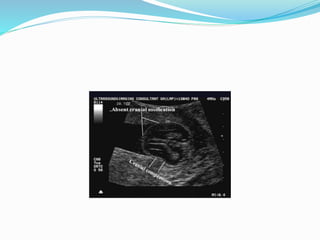

Thanatophoric Dysplasia

 Features:

 1- Short long bones well below the 3rd percentile

 2- Characteristic thickening of the metaphysis

 3-short splayed fingers (trident)

 4- Short ribs

 5- markedly small thorax

 6- Depressed nasal bridge + frontal bossing

Prognosis

 LETHAL

 Recurrence is low (dominant sporadic condition)

Thanatophoric Dysplasia  Features: 1- Short long bones well below the 3rd percentile  2- Characteristic thickening of the metaphysis  3-short splayed fingers (trident)  4- Short ribs  5- markedly small thorax  6- Depressed nasal bridge + frontal bossing

Prognosis  LETHAL  Recurrenceis low (dominant sporadic condition)